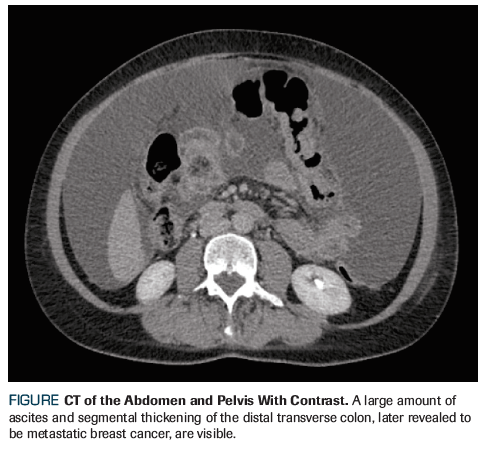

Figure. CT of the Abdomen and Pelvis With Contrast

Recently, the patient developed increasing abdominal pain, bloating, and constipation with smaller-caliber stools. Abdominal CT showed a mass in the transverse colon with ascites and peritoneal nodularity (Figure). No obvious liver metastasis or cirrhosis were present. Colonoscopy was attempted, but the stricture resulting from the colon mass was unable to be traversed. A palliative exploratory laparotomy with subtotal colectomy was performed due to impending complete obstruction. The pathology report revealed infiltration of poorly differentiated carcinoma-most consistent with breast primary-in the sampled small intestine, large intestine, appendix, and mesentery. Margins were positive. Immunologic stains were positive for mammaglobin, GATA binding protein 3 (GATA-3), and cytokeratin 7 (CK7). The sample was positive for ER (3+, 90%) and PR (3+, 5%) but negative for HER2. Following surgery, the patient’s normal bowel function returned, and she was referred to oncology for treatment of her newly diagnosed metastatic breast cancer.